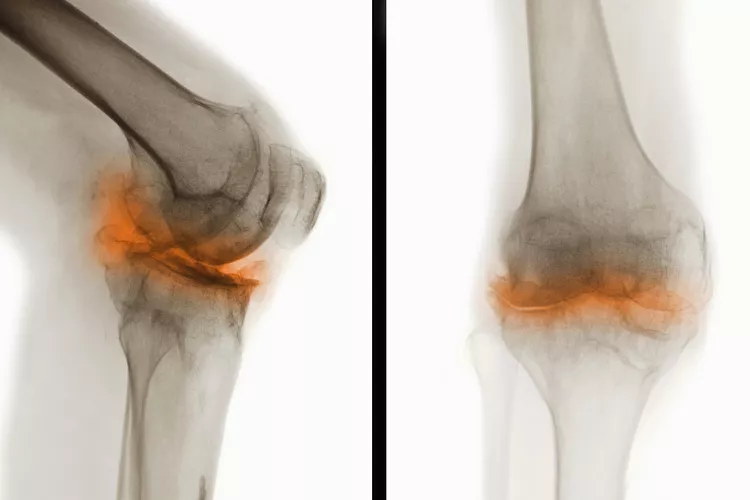

骨關(guān)節(jié)炎(Osteoarthritis, OA),一種常見(jiàn)的慢性關(guān)節(jié)疾病,主要特征是關(guān)節(jié)軟骨退化和關(guān)節(jié)邊緣骨質(zhì)增生。隨著病情進(jìn)展,骨關(guān)節(jié)炎不僅會(huì)導(dǎo)致關(guān)節(jié)疼痛和功能受限,還可能引發(fā)一系列并發(fā)癥,影響患者的整體健康和生活質(zhì)量。

在骨關(guān)節(jié)炎(OA) 中,覆蓋骨頭末端并幫助骨頭相互滑動(dòng)的光滑軟骨會(huì)逐漸磨損。這會(huì)導(dǎo)致骨頭相互摩擦和磨擦。

年齡、受傷和重復(fù)運(yùn)動(dòng)都可能導(dǎo)致骨關(guān)節(jié)炎,但最常見(jiàn)的原因是正常的磨損,尤其是在50歲以后。它可以發(fā)生在任何關(guān)節(jié)上,但最常見(jiàn)于手、膝蓋、臀部和脊柱。

骨關(guān)節(jié)炎是一種慢性疾病。骨關(guān)節(jié)炎無(wú)法治愈。一旦軟骨破裂,它就不會(huì)自行再生。隨著時(shí)間的推移,您可能會(huì)因患有骨關(guān)節(jié)炎而出現(xiàn)其他問(wèn)題或并發(fā)癥。